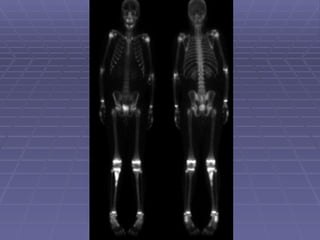

Whole body bone scan This is the bony phase of bone scan. Inject radiopharmaceutical and image in 2-4 hours. When we say bone scan, we usually mean whole body bone scan.

Whole body bonescan This is the bony phase of bone scan. Inject radiopharmaceutical and image in 2-4 hours. When we say bone scan, we usually mean whole body bone scan.